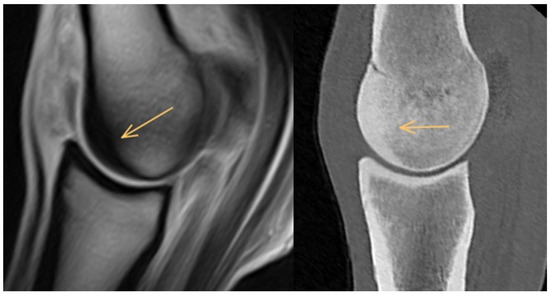

3.1. Third Metacarpal Bone